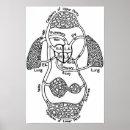

Human Lungs Medical Diagram Poster

PriceCA$39.05